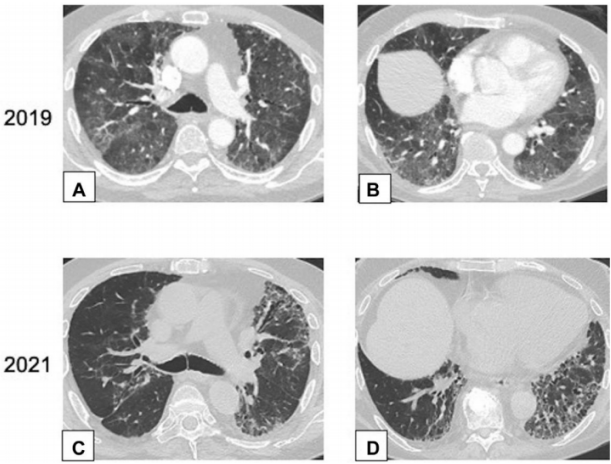

图源:Chest, 2022, 162(1):156-178.CT扫描图像显示双肺多发小实性结节(图8),提示恶性肿瘤或感染可能。CT扫描引导下针吸活检结果与OP诊断一致。图源:Chest, 2022, 162(1):156-178.42岁患者,病态肥胖,有呼吸困难,右肺上叶(图9A)和右肺下叶(图9B)CT平扫图像显示双侧、胸膜下或周围肿块样实变区域。这些发现为非特异性;活检结果提示OP,类固醇治疗后消退。图源:Chest, 2022, 162(1):156-178.OP以结节为主的影像学表现,范围从小的微结节(直径<4 mm)到较大的离散结节(直径通常达1 cm),以及较大的结节或肿块。较大的结节或肿块常被描述为具有不规则或锐利边缘,通常包含支气管充气征。图10所示为一名接受美沙拉嗪治疗的38岁男性溃疡性结肠炎患者出现气促。A为后外侧胸片,显示双肺多发结节。胸部CT增强扫描显示结节为周围型和支气管血管周围型,一些伴有气道扩张(B和C中的箭头)。粗针穿刺活检结果与OP相符。图源:Chest, 2022, 162(1):156-178.此外,结节可以单发或多发,通常为实性结节或部分实性结节。图11为一名73岁男性吸烟者低剂量CT,CT平扫图像显示右肺上叶孤立的不规则结节影,伴有细微的气道扩张(A中箭头)。支气管内超声引导下细针活检结果符合局灶性OP表现。图源:Chest, 2022, 162(1):156-178.临床中遇到影像学表现为结节的情况,需要注意与肿瘤相鉴别。PET扫描对这些病变的评估显示标准化摄取值轻微升高,但结果为非特异性,临床价值有限。图12所示为PET扫描一名无症状、有乳腺癌病史并长期使用呋喃妥因的70岁女性,CT平扫图像显示双肺下叶不规则、实性结节。由于担心转移性疾病,进行了PET扫描(图12C),轴位PET图像显示左肺下叶结节(B、C中箭头)是FDG高摄取。左肺下叶结节的粗针穿刺活检结果与OP相符。图源:Chest, 2022, 162(1):156-178.34岁女性患者因系统性红斑狼疮就诊,表现为气促。胸部CT显示双肺多发大小不等的实性结节,包括左肺基底部微小结节改变(图13A)。FDG-PET扫描的图像显示结节为高代谢(图13B)。两个结节的楔形活检结果符合OP诊断。图源:Chest, 2022, 162(1):156-178.以线状或网状为主的OP影像特点包括表现为线状不透明的实质条带,通常延伸到胸膜表面,先于磨玻璃影或实变。图14所示为条带活检证实为OP的同一患者间隔1年进行的CT扫描,可见患者双肺下叶条带部分消退(A、B中箭头)。